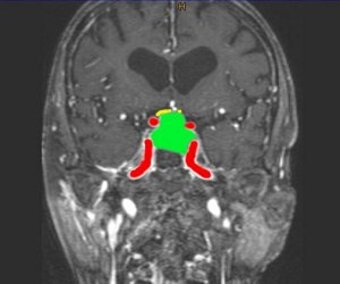

Abb. 1: Abbildung eines typischen kernspintomographischen Bildes eines Hypophysenmakroadenoms (Grün = Adenom, Rot = Hirnschlagader, Gelb = verlagerter Sehnerv).

Hypophysenadenome können aufgrund ihrer Größe und dadurch verursachten Raumforderung zu Kopfschmerzen und durch Druck auf den Sehnerv zu Sehstörungen führen. Auch kann es durch Druck auf die Hypophyse (Hirnanhangsdrüse) zu einer Unterfunktion der Hormonproduktion kommen (Hypophyseninsuffizienz).